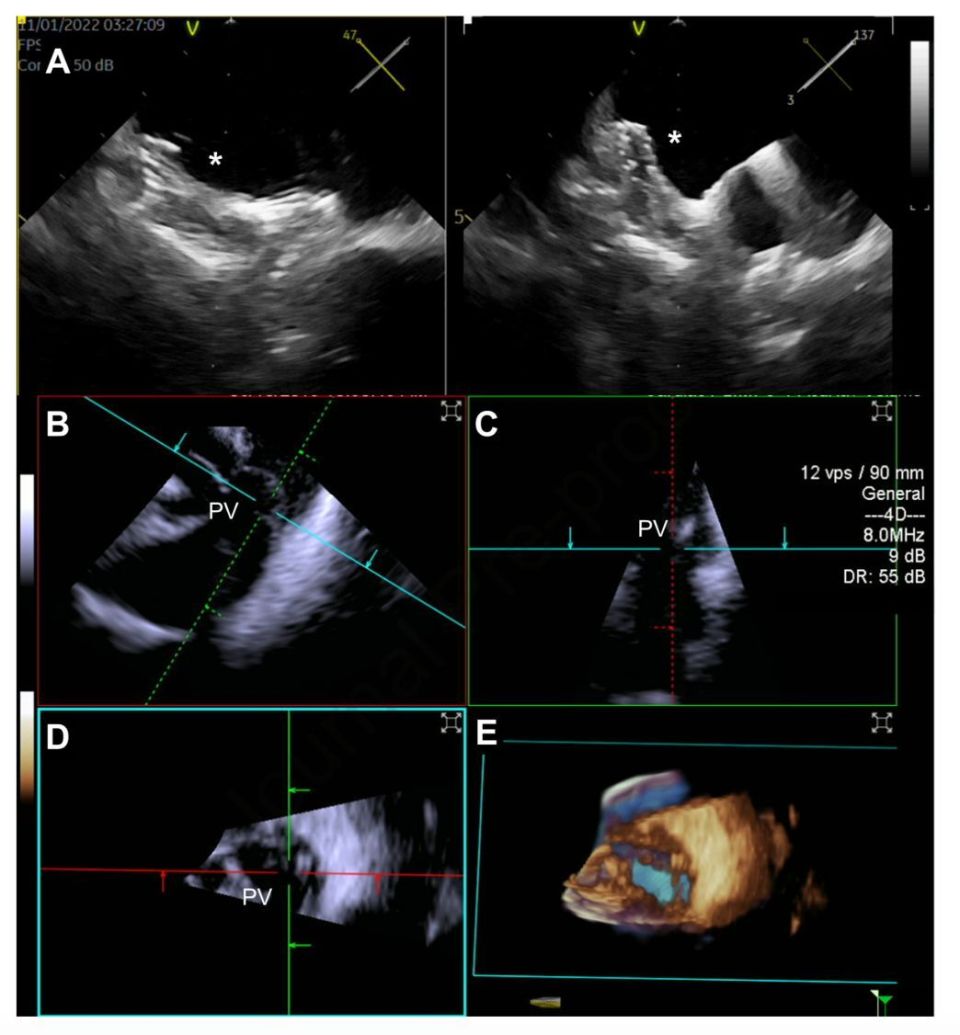

結構 超聲波

» 結構 性 超聲波 2d 3d 4d 分別 (99) 사진

結構 性 超聲波 2d 3d 4d 分別 (99) 사진